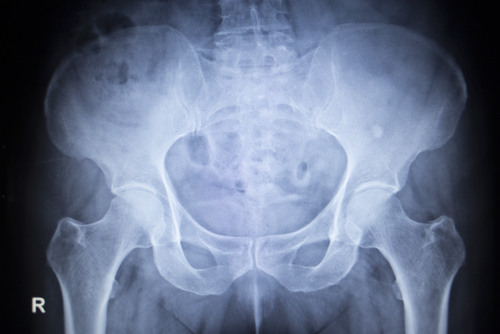

Een Cochrane-review van Puljak et al. zet het beschikbare bewijs voor celecoxib bij patiënten met artrose nog eens op een rij. Tussen 1999 en 2014 werden er 36 onderzoeken gevonden, die in totaal 9402 patiënten behandelden met celecoxib en deze vergeleken met placebo (n = 5935) of een andere NSAID (n = 1869). Er werd een klein positief effect van celecoxib op pijn en functie gezien ten opzichte van placebo. Daarnaast werd er een gunstiger bijwerkingenprofiel van celecoxib voor gastro-intestinale bloedingen gezien vergeleken met andere NSAID’s, maar de verdenking op een verhoogd risico op cardiovasculaire events bleef bestaan. Er werd wel veel mogelijke bias gesignaleerd.